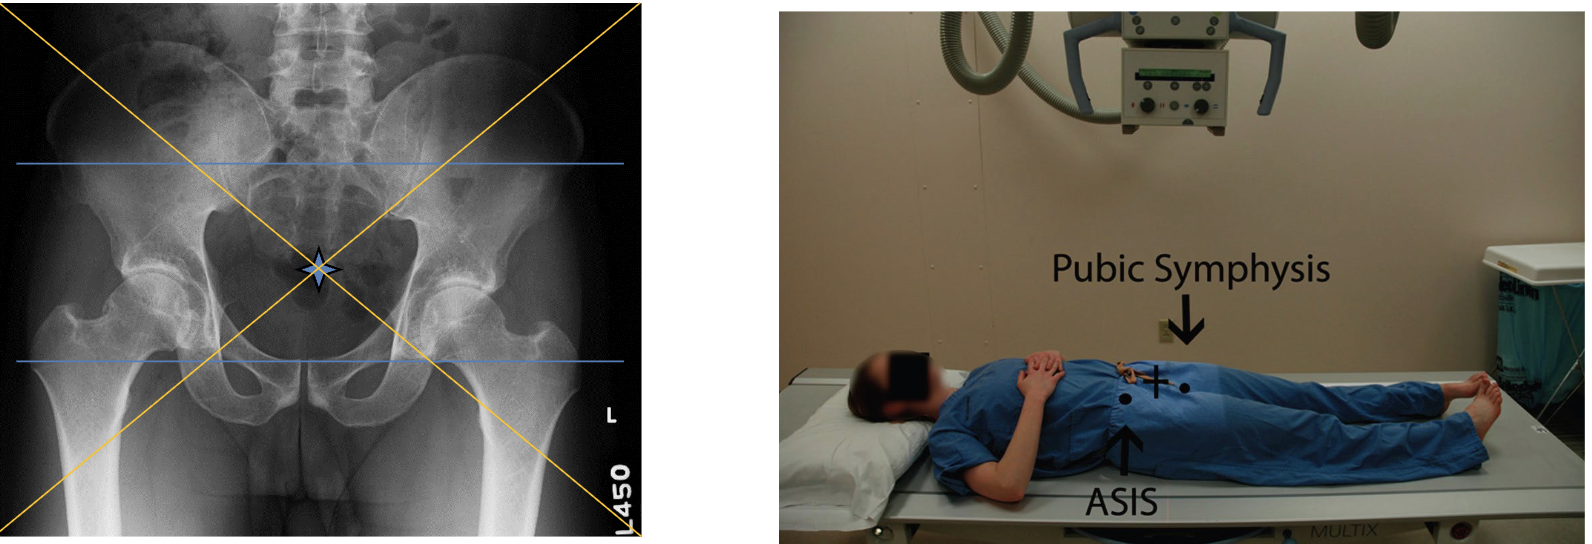

AP Pelvis

Broad FS, 100cm

78kVp, 25mAs

Straight tube

CR: midline 5cm superior to level of greater trochanter